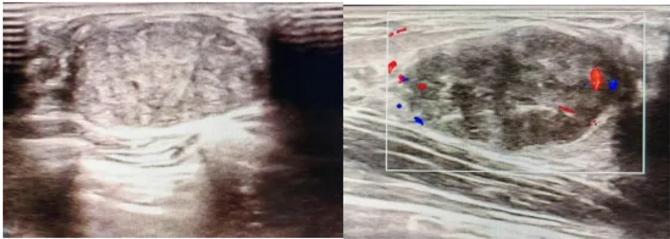

典型表現(xiàn):

橢圓形低回聲團(tuán)塊,包膜完整,內(nèi)部回聲均勻,后方回聲增強(qiáng),周邊無“蟹足樣”浸潤。

血流信號(hào):纖維瘤血流較少,惡性常伴豐富雜亂血流。

形態(tài):良性多呈橢圓形或分葉狀,邊界光滑。

縱橫比: 良性通常<1(橫徑>縱徑) 。